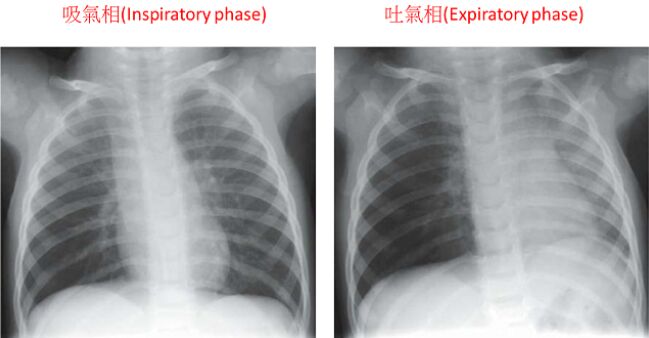

25.由下列兩張胸部X光片,判斷這位病童呼吸道異物最有可能的位置為何? (A)右側主支氣管(right main bronchus) (B)左側主支氣管(left main bronchus) (C)聲門下(subglottis) (D)氣管(trachea)